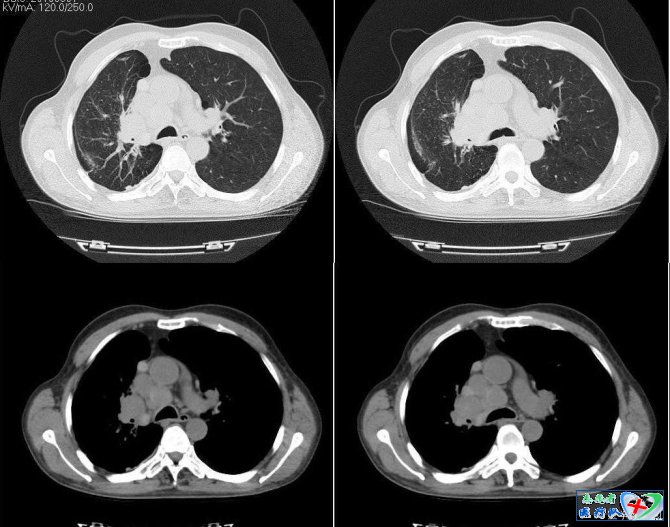

11、彗星尾征:

在胸部主要指由胸膜下肿块延伸至同侧肺门的线条状影。这种征象的形成,是由于当扭曲的血管、支气管走行至形似肿块的球形肺不张邻近区域时,支气管血管束似被牵拉进入肿块,形成像彗星尾样的征象。该征像是球形肺不张的典型征象。球形肺不张形成的机制,可能是刺激性的局限性胸膜炎,也有人认为是胸腔积液导致邻近的肺不张。球形肺不张的X线表现主要为胸膜下圆形或卵圆形,直径2.5~8.0cm,病灶与胸膜呈锐角,常不与膈面相连,相邻胸膜常见增厚,多为单发,偶见多发,多位于下叶,也可位于上叶。累及的肺叶体积常常缩小,其间可见支气管充气征。CT表现为肿块直径4~7公分,位于肺外周;肿块周边密度较高,中心可见充气支气管;肿块与胸膜成锐角;常出现胸膜瘢痕和胸膜增厚;支气管血管束似被牵拉进入肿块内;至少有两处边缘锐利;血管束进入的一侧边缘较模糊。